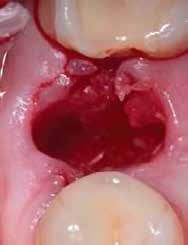

3. a–b ábrák: Fogeltávolítást követő alveolus prezerváció. – 4. a–b ábrák: Az implantátumok beültetése.

A fogak eltávolítása minimálinvazív módon történt, amelynek során a parodontális rostokat egy periotom segítségével átvágtuk, így lebenyes feltárásra nem volt szükség (3. a–b ábrák) . Az implantátumokat a frissen eltávolított fogak alveolusaiba ültettük be. A foghúzást követően minden alveolust alaposan ellenőriztünk az endodontiai, vagy parodontális eredetű gyulladásos szövetmaradványok eltávolítása érdekében, majd fiziológiás sóoldattal bőségesen átöblítettük. Megfelelő előfúrást követően a kerámiaimplantátumokat 30 fordulat/perc sebességgel és 35 Ncm behajtási nyomatékkal helyeztük be (4. a–b ábrák) . A réseket csontpótlóval töltöttük ki (Maxresorb ® 0,5–1,0 mm szemcseméret, 0,5 cm 3 térfogat, Straumann ®; 6. ábra ).